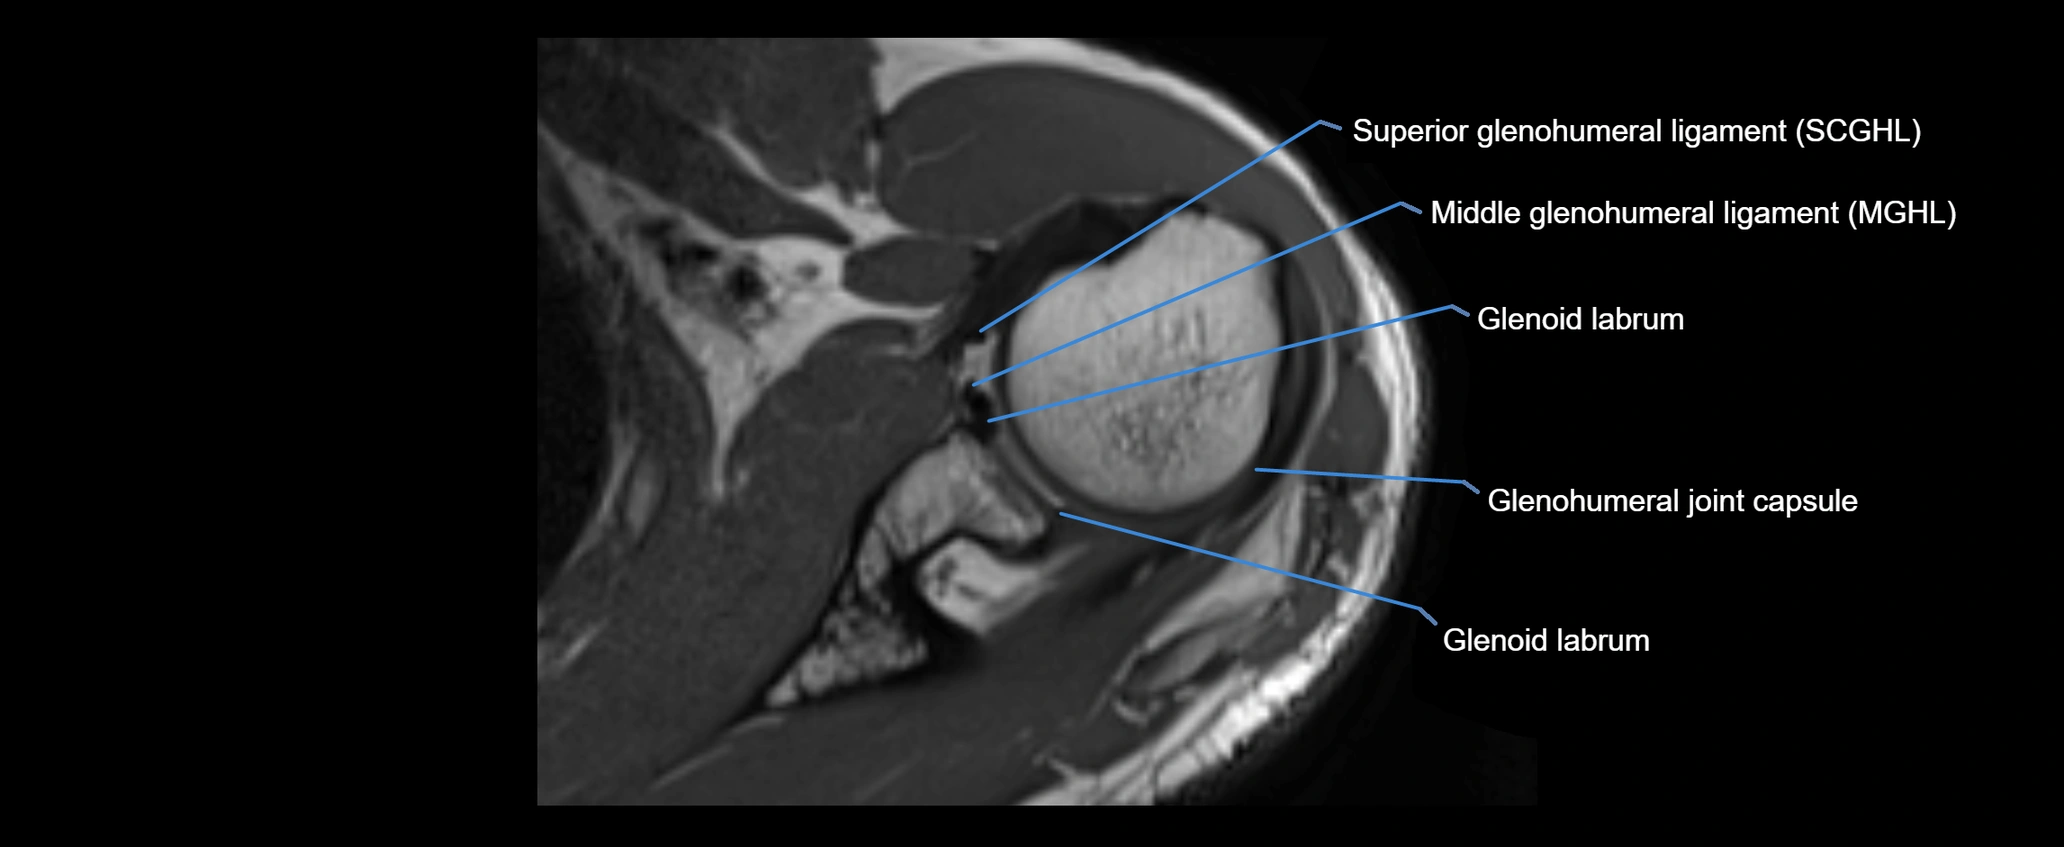

MRI Appearance

• T1-weighted images:

• Normal ligament: Low signal (dark linear band) spanning acromion to clavicle.

• Surrounding fat planes: Bright, delineating the ligament clearly.

• Marrow of clavicle and acromion: Bright due to fatty content.

• Tears: Discontinuity or irregular thickening with intermediate-to-bright signal.

• Chronic injury: Thinning, fraying, or irregular low-signal fibers with adjacent scarring.

• T2-weighted images:

• Normal ligament: Low signal, homogeneous.

• Partial tear or sprain: Focal hyperintensity or thickening.

• Complete tear: Discontinuity with fluid-bright gap between clavicle and acromion.

• Associated edema: Bright signal in distal clavicle or acromion marrow.

• Proton Density Fat-Saturated (PD FS):

• Normal ligament: Low signal, uniform thickness.

• Partial tear or sprain: Bright signal or contour irregularity.

• Complete tear: Clear discontinuity with bright signal gap and joint effusion.

• Excellent for assessing joint capsule, coracoclavicular ligaments, and periarticular edema.

CT image

image